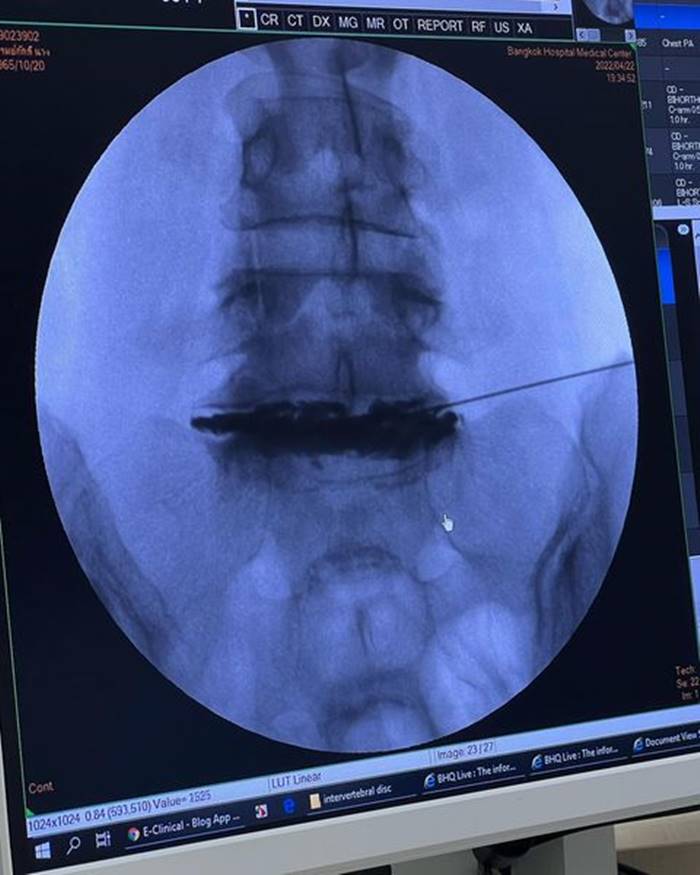

โดยเมื่อวันที่ 28 กรกฎาคม 2565 มาดามหนุ่ย ได้โพสต์ภาพเอกซเรย์กระดูกที่ถูกใส่เหล็ก พร้อมข้อความว่า "อยากขอเตือนเพื่อน ๆ นะคะ ว่าถ้าออกกำลังท่าไหนแล้วรู้ตัวว่าไม่ไหวก็ให้บอก trainer ค่ะ อย่าฝืนทำ เพราะลงท้ายอาจจะต้องผ่าตัดแบบหนุ่ย.. trainer ให้ทำ squat ที่หนุ่ยก็หันไปบอกแล้วว่าหนักไปทำไม่ได้เค้าก็ยังให้ทำ ผลคือหมอนรองกระดูกปลิ้น ต้องผ่าตัดใส่เหล็กตามภาพเลยค่ะ..ตอนนี้ก็ต้อง slowlife ไป 4-5 เดือน"